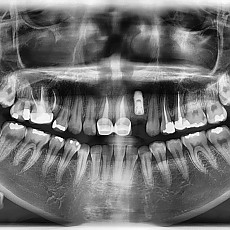

시술전후사진 4 페이지

Total 62건 4 페이지